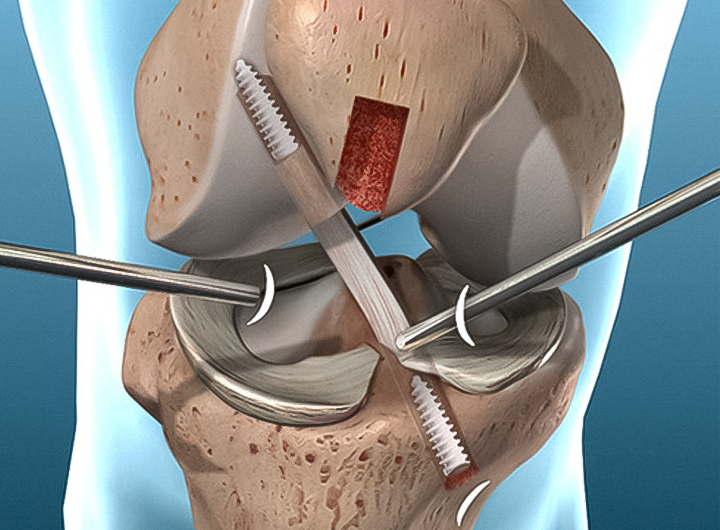

QUANDO OPERAR O LIGAMENTO CRUZADO ANTERIOR?

Quando há o rompimento do LCA, o tratamento cirúrgico costuma ser a abordagem mais indicada, uma vez que o ligamento não é capaz de cicatrizar por conta própria.

Caso haja cicatrização, ela tende a ocorrer de maneira incorreta, dificultando a funcionalidade da articulação.